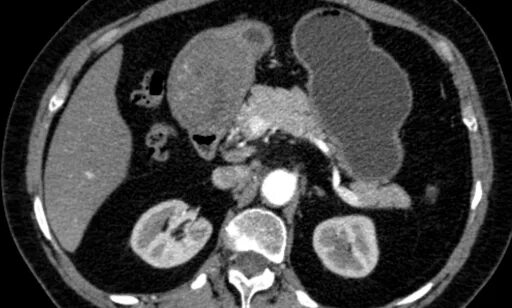

Язва желудка кт